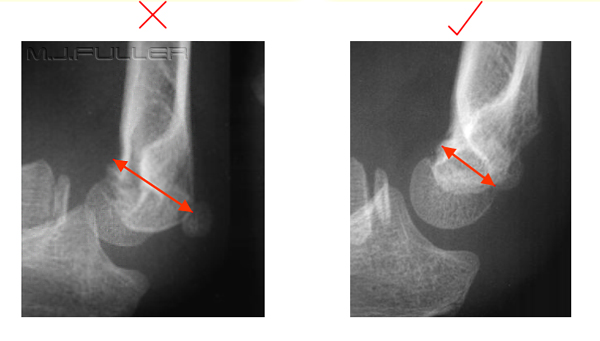

humeral line anterior elbow supracondylar pediatric fractures normal radiology fracture humerus radiopaedia capitellum angle capitulum joint case types injuries occult

elbow ray radial fracture head normal alignment line anterior humeral coreem

elbow forearm normal lateral alignment anterior capitellum radiograph interpreting radiographs fracture supracondylar intersect

elbow line anterior normal radiocapitellar humeral fractures adults lateral radiograph dislocations imaging

humeral radiocapitellar elbow radiographic

elbow humeral fracture supracondylar forearm capitellum radiographs interpreting intersect

radiopaedia line humeral anterior radiology

elbow paediatric wikiradiography minimal ap antero posterior distance lateral

capitellum dislocation elbow pediatric through drawn lateral anterior humeral pass should line

Anterior humeral line. Pediatric humeral fracture. Elbow injuries